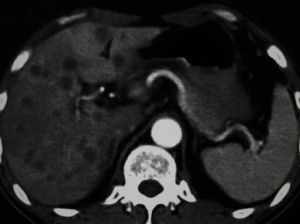

B超:肝內單發或多髮結節,可為低回聲、強回聲或不均勻回聲,腫塊內部回聲為高回聲,周圍包繞寬0.5~1cm的低回聲聲暈,偶爾有的高回聲中央可有少許低回聲區或無回聲區,為癌腫中心出血、壞死所致,此即為“牛眼征”,或稱“靶環征”。CT增強示:腫瘤強化,境界清楚,中央密度多低於周圍部,腫瘤邊緣可顯示環形不規則強化,部分可見“牛眼征”,表現為病灶中心為低密度,邊緣為高密度強化,最外層密度又低於肝實質。

該徵象被認為是轉移性肝癌典型影像表現,可見於任何轉移型肝癌,但多見於腺癌的肝轉移。

CT“牛眼征”